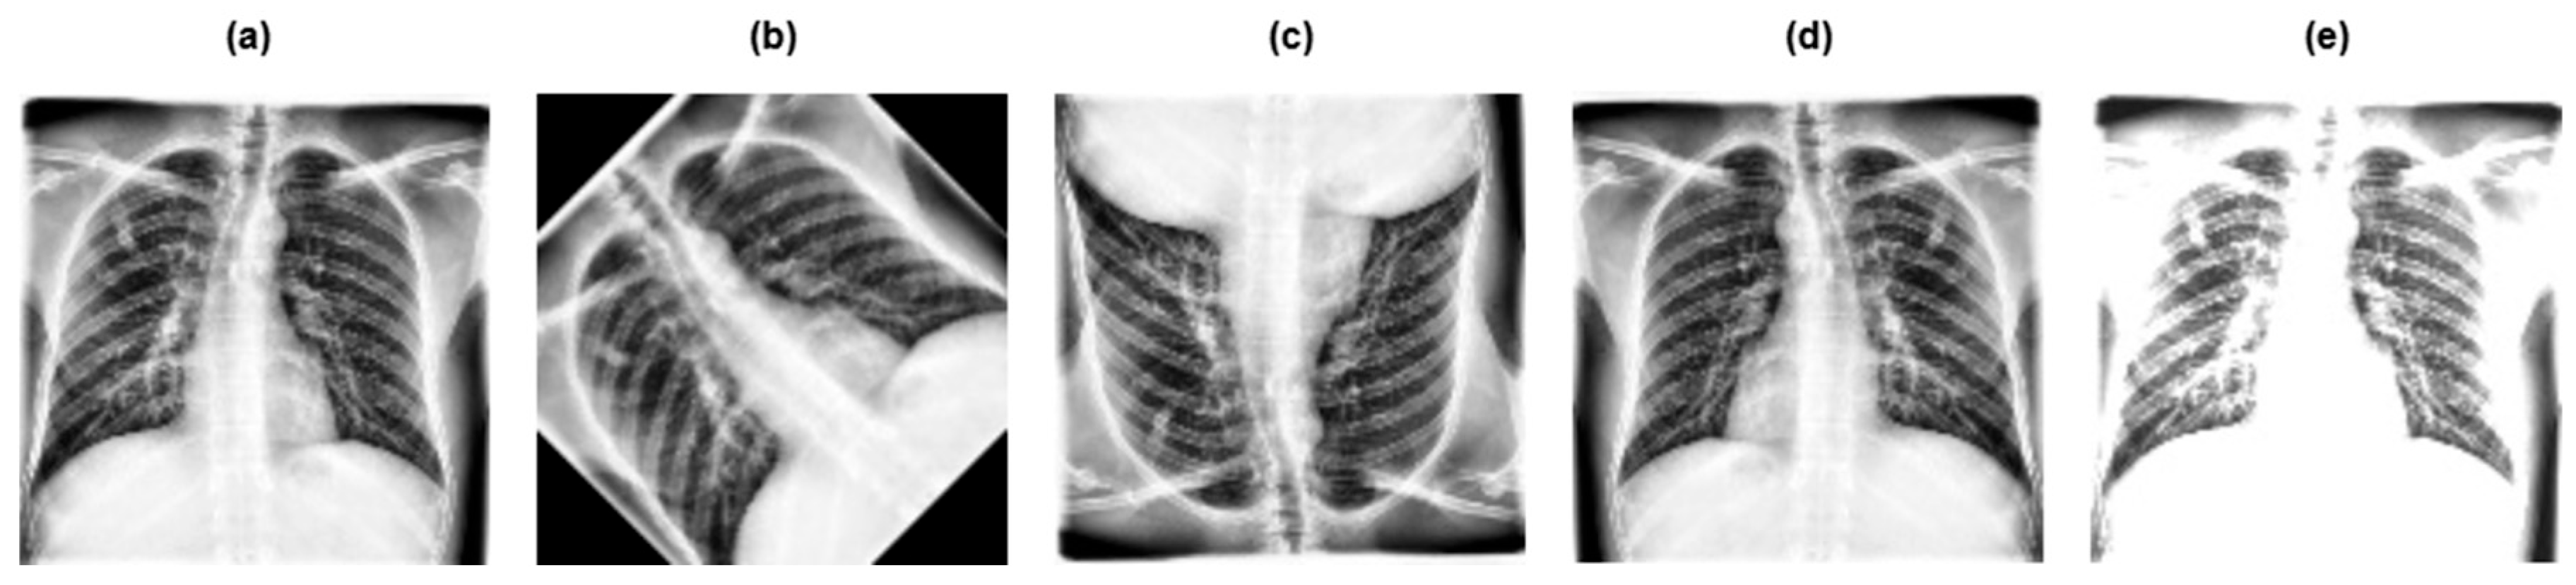

3.2. Data Preprocessing

- •

- Grayscaling: This refers to the conversion of RGB images to grayscale.

- Image resizing: The grayscale image was rescaled to a particular size, that is 128 × 128 pixels.

- Contrast Limited Adaptive Histogram Equalization (CLAHE): This improves the contrast of the image, making the tuberculosis area more pronounced and clearer.

- Image normalization: Normalization adapts the intensity range of individual pixels, typically to make the pixel values of an image more consistent and uniform to the human eye.

3.3. Data Augmentation